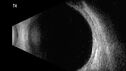

Albinism and Renal failure - Possible Hermansky-Pudlak Syndrome72 views65 year old female with foveal hypoplasia and renal failure since age 18. VA 20/40 OD, 20/63 OSDec 21, 2024

Albinism and Renal failure - Possible Hermansky-Pudlak Syndrome66 views65 year old female with foveal hypoplasia and renal failure since age 18. VA 20/40 OD, 20/63 OSDec 21, 2024

Albinism and Renal failure - Possible Hermansky-Pudlak Syndrome73 views65 year old female with foveal hypoplasia and renal failure since age 18. VA 20/40 OD, 20/63 OSDec 21, 2024